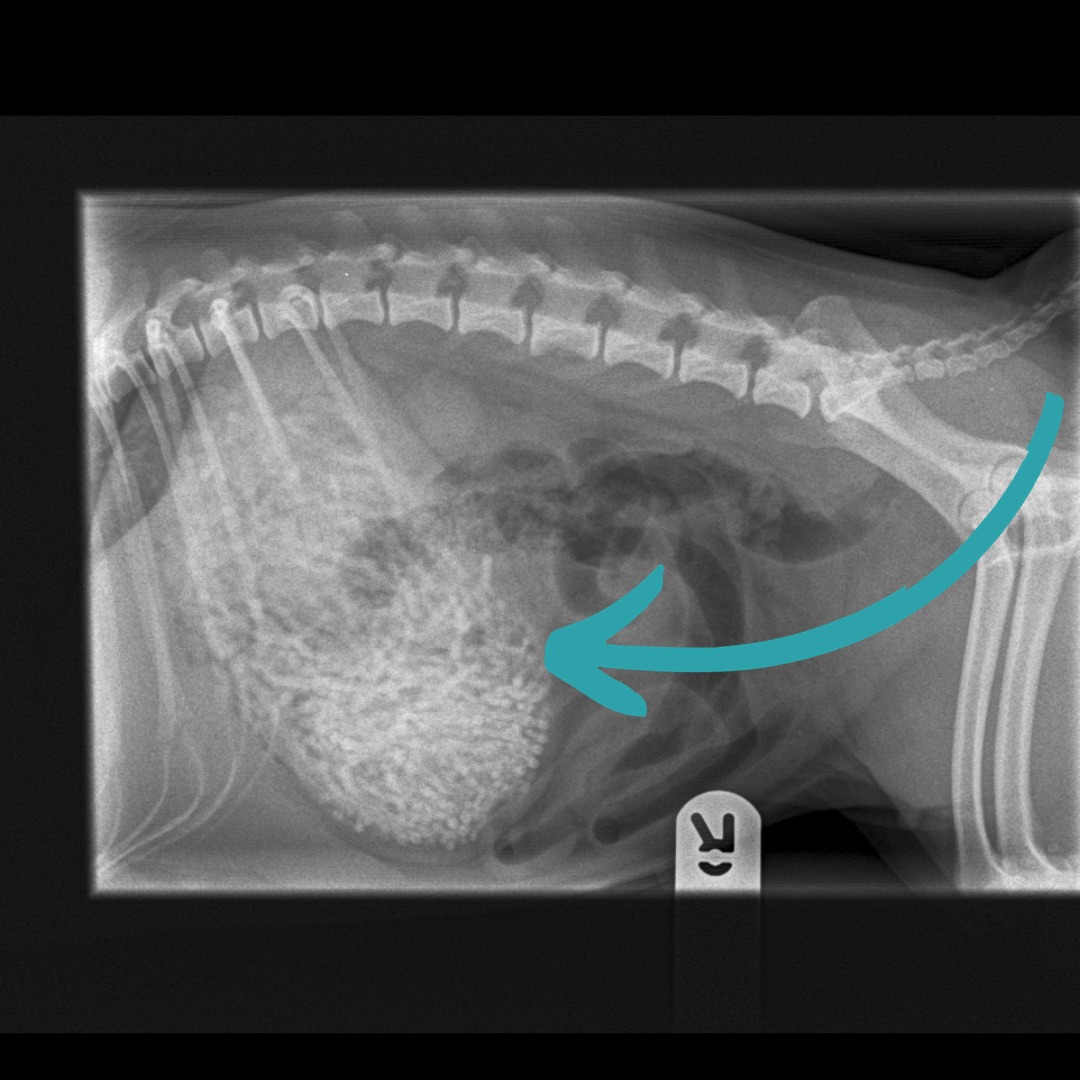

Prvi pregled u veterinarskoj ordinaciji Newton Clarke pokazao je da pas ima nešto neobično u stomaku, pa su se odmah odlučili na operaciju.

Veterinarka Emily Whitby rekla je da su uklonili 50 do 60 gumica teških 200 grama - Ham je teška samo šest kilograma.